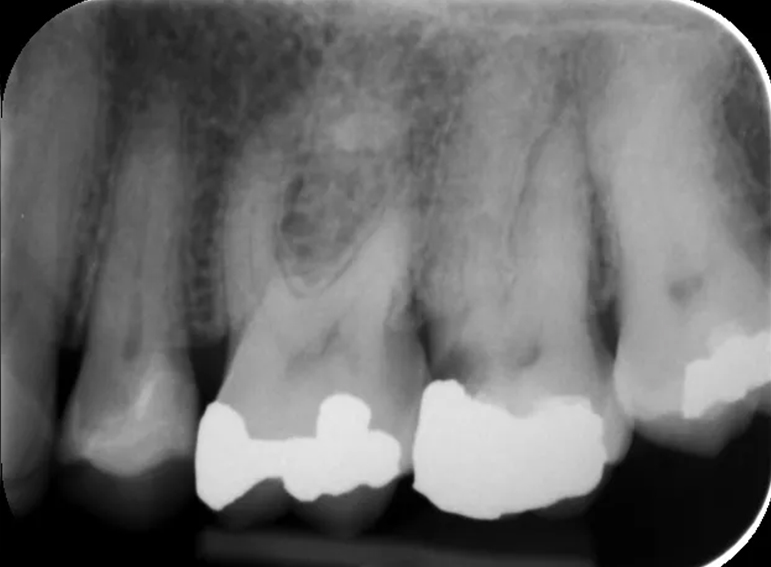

Separated instrument management on a sclerosed upper second molar.